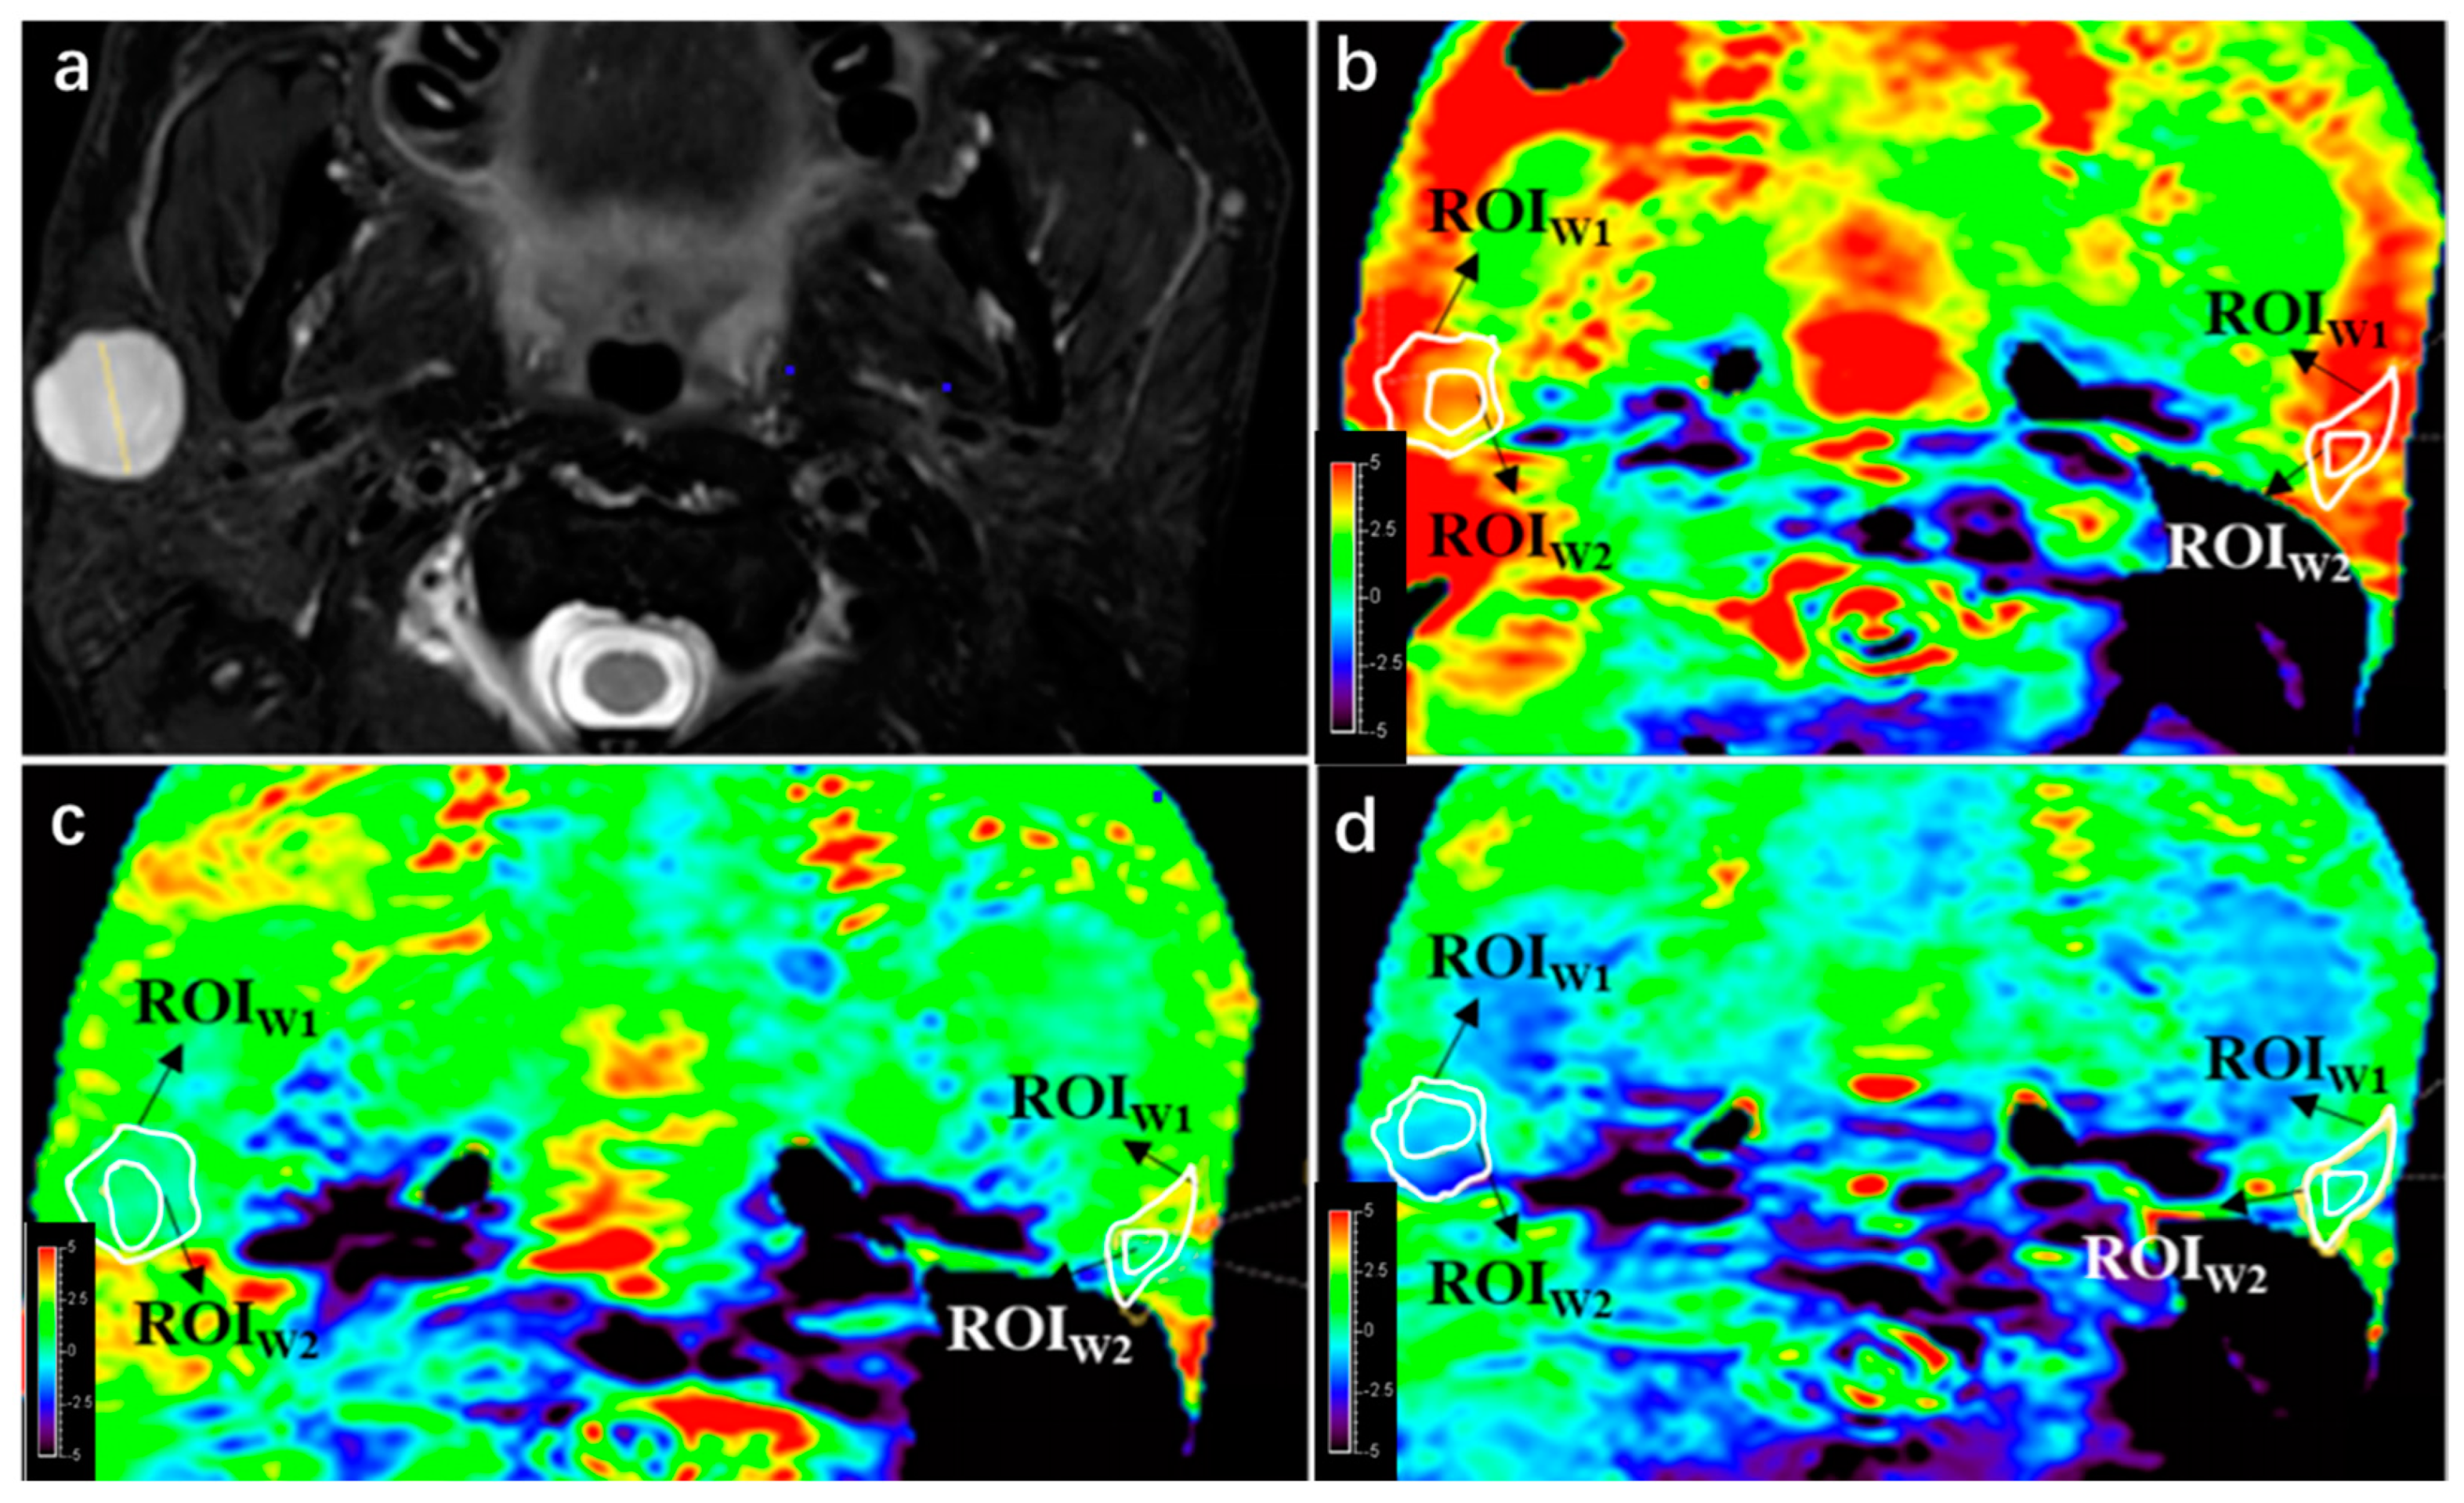

Figure 3.

APTw image quality change with B1 power change. (a) A lesion was found at right side of parotid gland in this 42-year-old male on T2WI, a pathologically proven pleomorphic adenoma. (b) APTw image with B1 = 2 μT; integrity scores of the lesion and parotid gland were both 4, while hyperintensity artifact scores were 3 and 2, respectively. (c) APTw image with B1 = 1 μT; integrity scores of the lesion and parotid gland were both 4, respectively, while hyperintensity artifact scores were both 4. (d) APTw image with B1 = 0.7 μT; integrity scores of the lesion and parotid gland were 3 and 4, respectively, while hyperintensity artifact scores were both 4.

The results of the comparison among the three APTw sequences (APT1, APT2, and APT3) showed that PTs had better integrity in APT 1 compared to APT 2, and APT 2 had better integrity compared to APT 3. However, there was no significant difference in integrity between the three sequences for PGs. In terms of hyperintensity artifacts, lesions in both APT 2 and APT3 had less hyperintensity artifacts compared to APT1 (p < 0.05), while there was no significant difference in hyperintensity artifacts between APT 2 and APT 3 for PTs (p = 0.157). Similarly, PTs in APT 2 and APT 3 also had less hyperintensity artifacts compared to APT 1 (p < 0.05), and there was no significant difference between APT 2 and APT 3 (p = 0.083). Further details can be seen in Table 6.